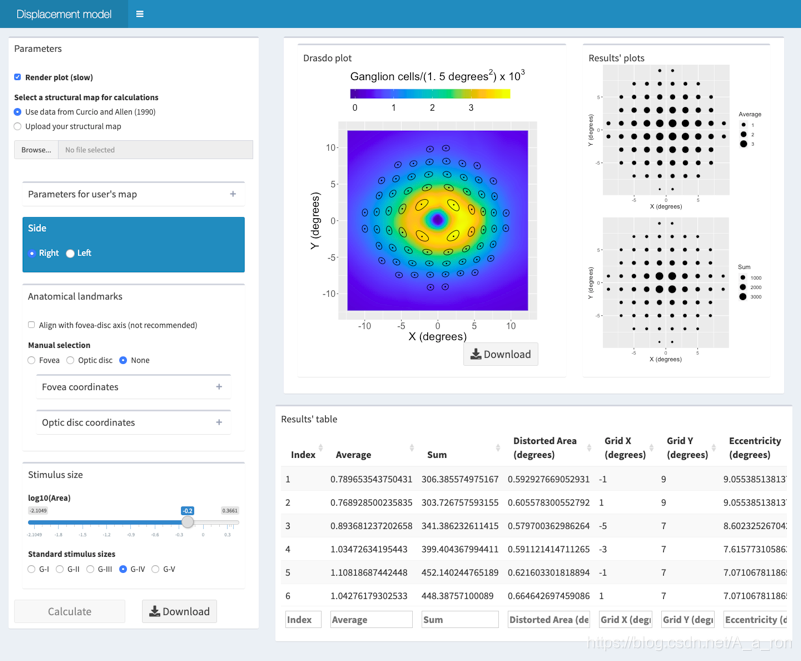

3. AURA tools

AURA tools : AUtomated Retinal Analysis tools,一系列的与OCT影像处理相关的工具集,主要有:

- ASiMOV-0.1.zip

- N3Ov1.0.zip (对OCT图像中的强度不均匀性进行校正)

- OCTLayerSegmentation2.11.zip

项目主页对该工具的介绍和使用较少,不过提供了可直接下载的链接,有需要的同学可以下载下来试一试。